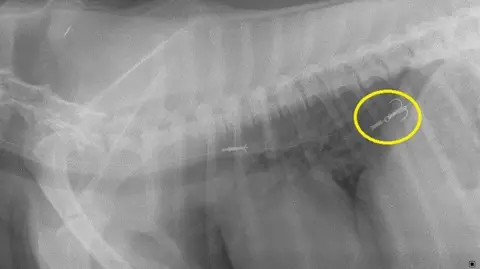

"A microchip can be changed or removed from a dog but the DNA cannot be changed or altered, it is unique to that pet.